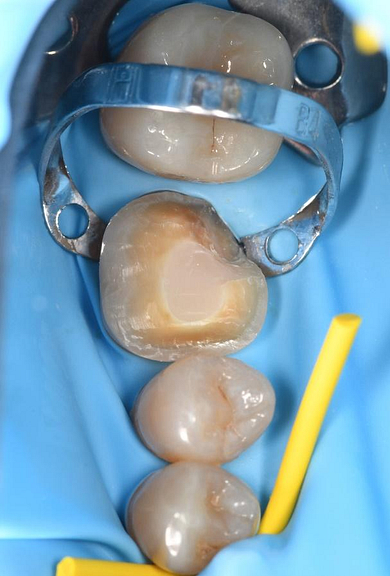

His previous dentist retired, and the patient visited me for the first time as an emergency visit due to symptomatic irreversible pulpitis from a cracked tooth (46). Root canal treatment on tooth 46 was completed, and a crown placed.

Upon completing a comprehensive examination, it was revealed that teeth 25 and 26 were also cracked, and the patient expressed interest in replacing the missing tooth 24.

The treatment plan consisted of crowning teeth 25 and 26, replacing missing tooth 24 with a dental implant, and placing a bone graft to replace lost bone tissue and provide a stable foundation for the implant.